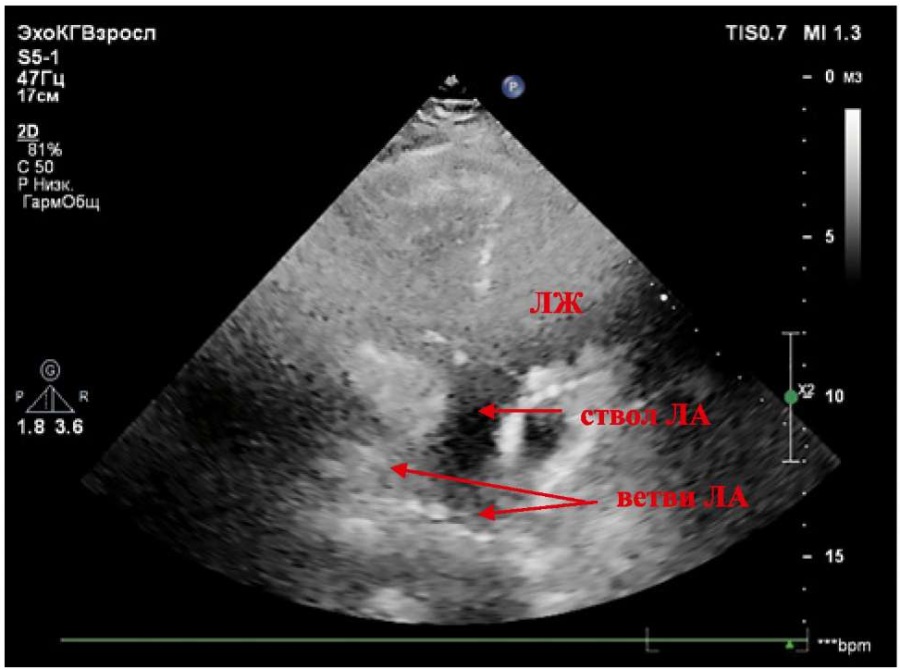

При проведении ЭхоКГ, представленной на рисунках 1–4, выявлено правосформированное леворасположенное сердце. Печень расположена в анатомически положенном месте (справа). Анатомически ПП (ориентир — заслонка полой вены) соединён с анатомически ЛЖ (анатомический ориентир — гладкая эндокардиальная поверхность), расположенным справа (дискордантное АВ-соединение). Диаметр ПП — 36×42 мм. Базальный диаметр ЛЖ из апикальной позиции (приточный отдел) — 38 мм, глобальная сократимость не снижена. Толщина боковой стенки ЛЖ — 7–8 мм. ПП соединяется с ЛЖ посредством двустворчатого (анатомически митрального) клапана, крепление створок которого расположено ниже крепления створок ТК. Митральная регургитация (+/++). От анатомически ЛЖ отходит ствол ЛА (несёт венозную кровь), с наличием митрально-легочного фиброзного продолжения. Диаметр ЛА на уровне клапана — 26 мм. Максимальный градиент на клапане ЛА — 8 мм рт. ст. Пульмональная регургитация (+). Визуализируются бифуркация и ветви ЛА, не расширены. Слева от ЛЖ располагается анатомически ПЖ (анатомический ориентир — модераторный пучок и трабекулярность). ПЖ соединяется с анатомически ЛП посредством анатомически ТК. Трикуспидальная регургитация (++/+++), створки утолщены. Сухожильные хорды ТК крепятся к перегородке и трабекулам ПЖ. Базальный диаметр ПЖ из апикальной позиции — 49 мм. Фракция изменения площади (ФИП) ПЖ — 40% (норма — более 35%) [7][8]. Систолическая экскурсия плоскости трикуспидального кольца в М-режиме (TAPSE) — 14,7 мм (норма — более 17 мм) [7][8]. Толщина боковой стенки ПЖ — 7–8 мм, МЖП — 9 мм. Диаметр ЛП — 46×68 мм. Объём ЛП — 80 мл. От анатомически ПЖ отходит Ао (несёт артериальную кровь). Диаметр корня Ао — 34 мм, восходящего отдела Ао — 29 мм, дуга Ао — 29 мм. Аортальный клапан (АК) двухстворчатый, регургитации нет. Максимальный градиент на АК — 8 мм рт. ст. Скорость кровотока в нисходящем отделе Ао в пределах нормы. Отсутствует контакт между артериальным (анатомически ТК) АВ-клапаном и магистральным сосудом (Ао), что свидетельствует об инверсионном положении сосудов. Ао расположена спереди и слева от ЛА. Патологические шунты через МПП и МЖП при цветовом картировании не регистрируются, смещения септальной створки ТК нет. Допплер: ЕТК — 108 см/сек., АТК — 32 см/сек., ебокТК — 19 см/сек., еМЖП — 11,7 см/сек., sТК — 8 см/сек. (норма для ТК — более 9,5 см/сек.) [7], что позволяет косвенно судить о наличии нарушения регионарной систолической функции ПЖ. ta-eТК — 625 мс, tsТК — 354 мс, Teim-индекс — 0,77 (норма — менее 0,54), что также косвенно указывает на наличие нарушения регионарной систолической функции ПЖ. Е/еТКср 7,5 — косвенный признак отсутствия высокого конечного диастолического давления в ПЖ [7][8].

Рисунок 4. Апикальная пятикамерная позиция. Отхождение ствола лёгочной артерии от левого желудочка. Отмечается митрально-легочное фиброзное продолжение.

Примечание: ЛЖ — левый желудочек, ЛА — лёгочная артерия.

Figure 4. Apical five-chamber view. Origin of the pulmonary artery trunk from the left ventricle. Mitral-pulmonary fibrous continuation is noted.

Note: LV — left ventricle, PA — pulmonary artery.